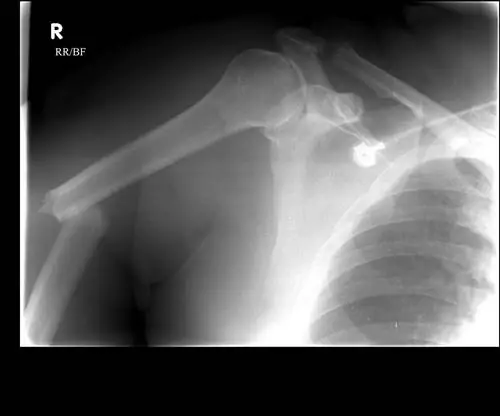

Переломы проксимального отдела плечевой кости

Верхушка плечевой кости - шаровидная часть шаровидного сустава плеча. Переломы рядом с ним считаются переломами проксимального отдела плечевой кости.

Эти переломы могут затрагивать ротаторную манжету плеча, группу тканей, которые соединяют мышцы с костями вокруг плеча.